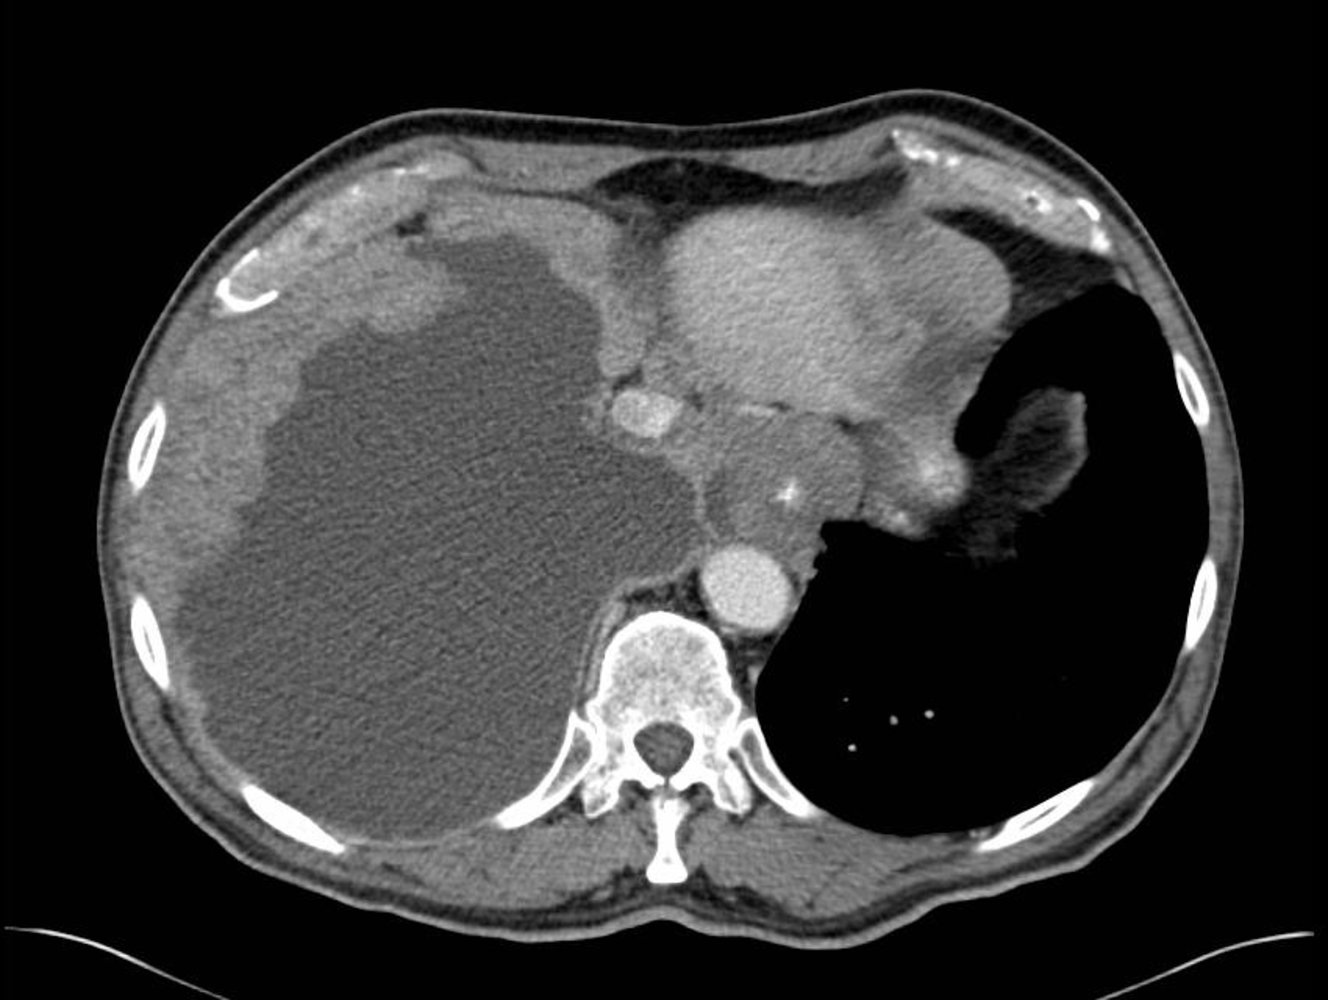

Initial imaging

• Modalities

• Chest x-ray: often routinely obtained first

• Contrast-enhanced CT: most sensitive imaging modality for diagnosis

• Findings in pleural mesothelioma

• Multiple nodular pleural lesions (pleural thickening)

• Pleural effusion

• Thickening of interlobar fissures

• Pleural opacities (calcifications or plaques)

• Signs of local tumor growth, e.g., reduced size of ipsilaterallung fields, mediastinal shift

• Signs of local invasiveness, e.g., obliteration of fat planes